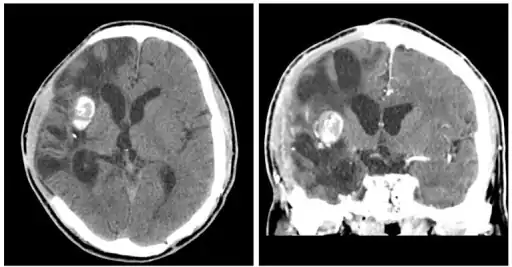

| Brain abscess in a person with a CSF shunt.[1] | |

MRI (T1 with contrast) showing the ring-enhancing lesion. From a rare case report of an abscess formed as a complication of the CSF shunt. Jamjoom et al., 2009.[1]

The diagnosis is established by a computed tomography (CT) (with contrast) examination. At the initial phase of the inflammation (which is referred to as cerebritis), the immature lesion does not have a capsule and it may be difficult to distinguish it from other space-occupying lesions or infarcts of the brain. Within 4–5 days the inflammation and the concomitant dead brain tissue are surrounded with a capsule, which gives the lesion the famous ring-enhancing lesion appearance on CT examination with contrast (since intravenously applied contrast material can not pass through the capsule, it is collected around the lesion and looks as a ring surrounding the relatively dark lesion). Lumbar puncture procedure, which is performed in many infectious disorders of the central nervous system is contraindicated in this condition (as it is in all space-occupying lesions of the brain) because removing a certain portion of the cerebrospinal fluid may alter the concrete intracranial pressure balances and causes the brain tissue to move across structures within the skull (brain herniation).

Ring enhancement may also be observed in cerebral hemorrhages (bleeding) and some brain tumors. However, in the presence of the rapidly progressive course with fever, focal neurologic findings (hemiparesis, aphasia etc.) and signs of increased intracranial pressure, the most likely diagnosis should be the brain abscess.